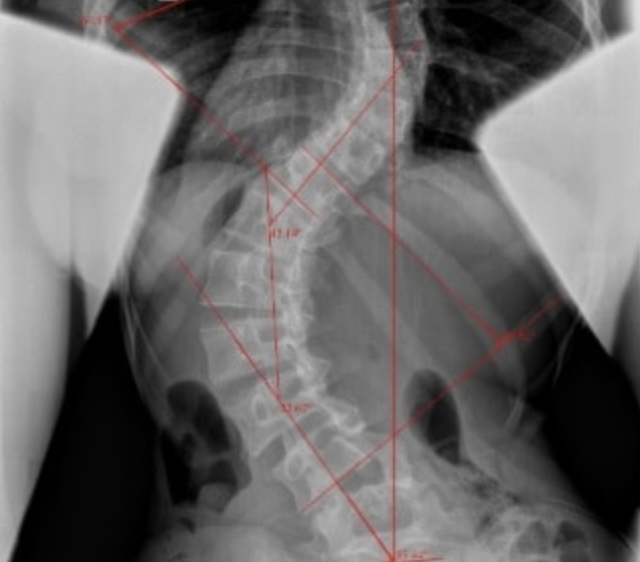

John contacted me about his wife who had a severe scoliosis, and he wanted to know if I could help. After he explained to me about his wife's condition it seemed clear that although she had low back pain, her scoliosis appeared to be the root cause of this.

I recommended that his wife should see a Schroth practitioner before working with me. While I often have clients who have a mild scoliosis that's incidental to their low back pain, I am not a specialist in treating severe cases of scoliosis that are the primary cause of someone's pain. My policy is to refer out cases like these.